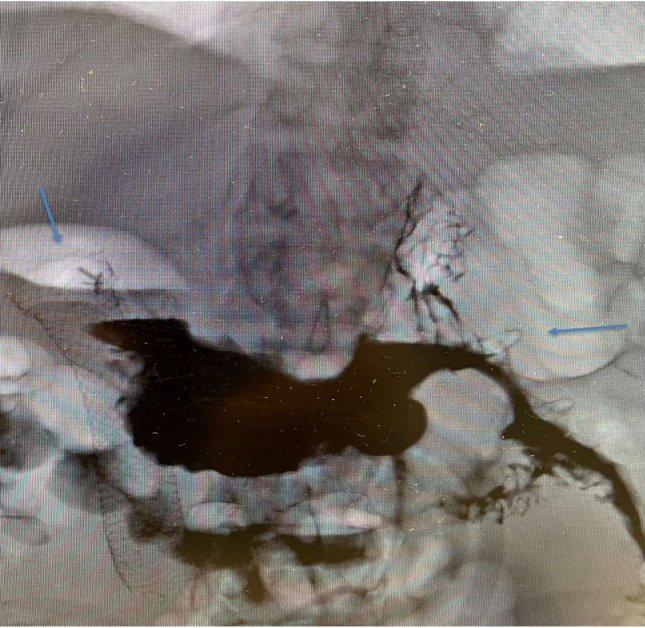

Using a therapeutic double channel gastroscope (Olympus, USA) a biliary cannula with guide wire was passed through the obstructed duodenum under fluoroscopy using contrast injection. The guide wire was successfully passed beyond the obstructed duodenum into the proximal jejunum. Then 7 Fr nasobiliary tube was passed over the guide wire all the way to the proximal jejunum. The gastroscope was removed leaving the nasobiliary cannula in place. The therapeutic linear echoendoscope (Olympus, USA) was passed intothe stomach. Diluted contrast with saline and methylene blue was instilled into the jejunum. Using both fluoroscopy and ultrasound imaging via the echoendoscope, proximal jejunum was identified. A 19-gauge needle was passed to the jejunum and the blue colored diluted contrast was successfully aspirated confirming the correct location. An electrocautery enhanced 15 mm x 15 mm lumen-apposing metal stent (LAMS) was successfully deployed (Fig. 3). Endoscopy confirmed the good location and the small bowel was seen through the stent from the stomach. Upper GI contrast study confirmed the creation of gastroenterostomy and it did not show any leak. The patient was started on liquid diet and slowly progressed to low residue diet. His nausea and vomiting completely subsided. He was able to tolerate low residue diet well. EUS guided gastroenterostomy is a minimally invasive non-surgical technique for patients with malignant duodenal or gastric outlet obstructions.

Figure 3. UGI contrast study showing the contrast from the stomach draining through LAMS 15 mm x 15 mm on the right hand side (thick arrow) emptying into the proximal jejunum. Duodenal stent seen on the left hand side (thin arrow) of the picture.

Figure 3